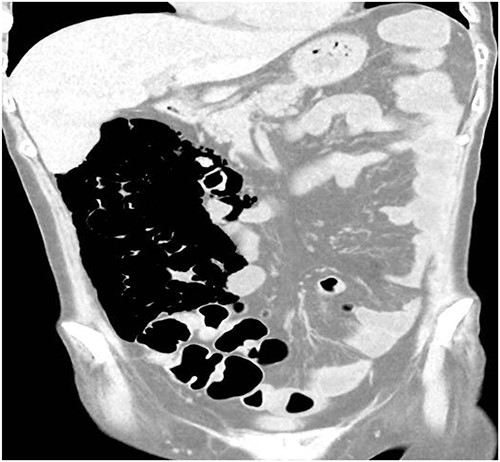

A 49-year-old female with a background of stage IV diffuse large B-cell lymphoma and subsequent graft-versus-host disease from a bone marrow transplant presented to a rural hospital in New South Wales, Australia with 12-h history of painless per rectal bleeding and fever. On examination she had a soft, but distended abdomen. Laboratory investigations revealed thrombocytopenia and hypokalaemia. Computed tomography of the abdomen and pelvis had a bizarre appearance due to pneumatosis cystoides coli extending from the ileocaecal junction to the mid-transverse colon. Given her benign abdominal examination, her management was initially supportive with intravenous antibiotics, intravenous fluid resuscitation and correction of electrolyte abnormalities.

A 49-year-old female with a background of stage IV diffuse large B-cell lymphoma and subsequent chronic graft-versus-host disease (cGVHD) from a bone marrow transplant presented to a rural referral hospital in New South Wales with a 12-h history of painless per rectal bleeding and fever. She had undergone her last cycle of chemotherapy 12 months prior and her cGVHD was being treated with dexamethasone mouthwash, oral cyclosporine and an infusion of rituximab, administered the day prior to this presentation. On examination she had a soft, but distended abdomen. Laboratory investigations revealed thrombocytopenia and hypokalaemia. Computed tomography (CT) of the abdomen and pelvis had a bizarre appearance due to pneumatosis cystoides coli extending from the ileocaecal junction to the mid-transverse colon (Figs 1–3). A chest X-ray was also taken, which shows evidence transmural air within the ascending colon, including the hepatic junction (Fig. 4). Given her benign abdominal examination, her management was initially supportive with intravenous antibiotics, intravenous fluid resuscitation and correction of electrolyte abnormalities. She was subsequently transferred to a metropolitan tertiary hospital, under her usual treating haematologist with consultation by the colorectal surgical team. She recovered and did not require any acute surgical intervention for pneumatosis cystoides coli.